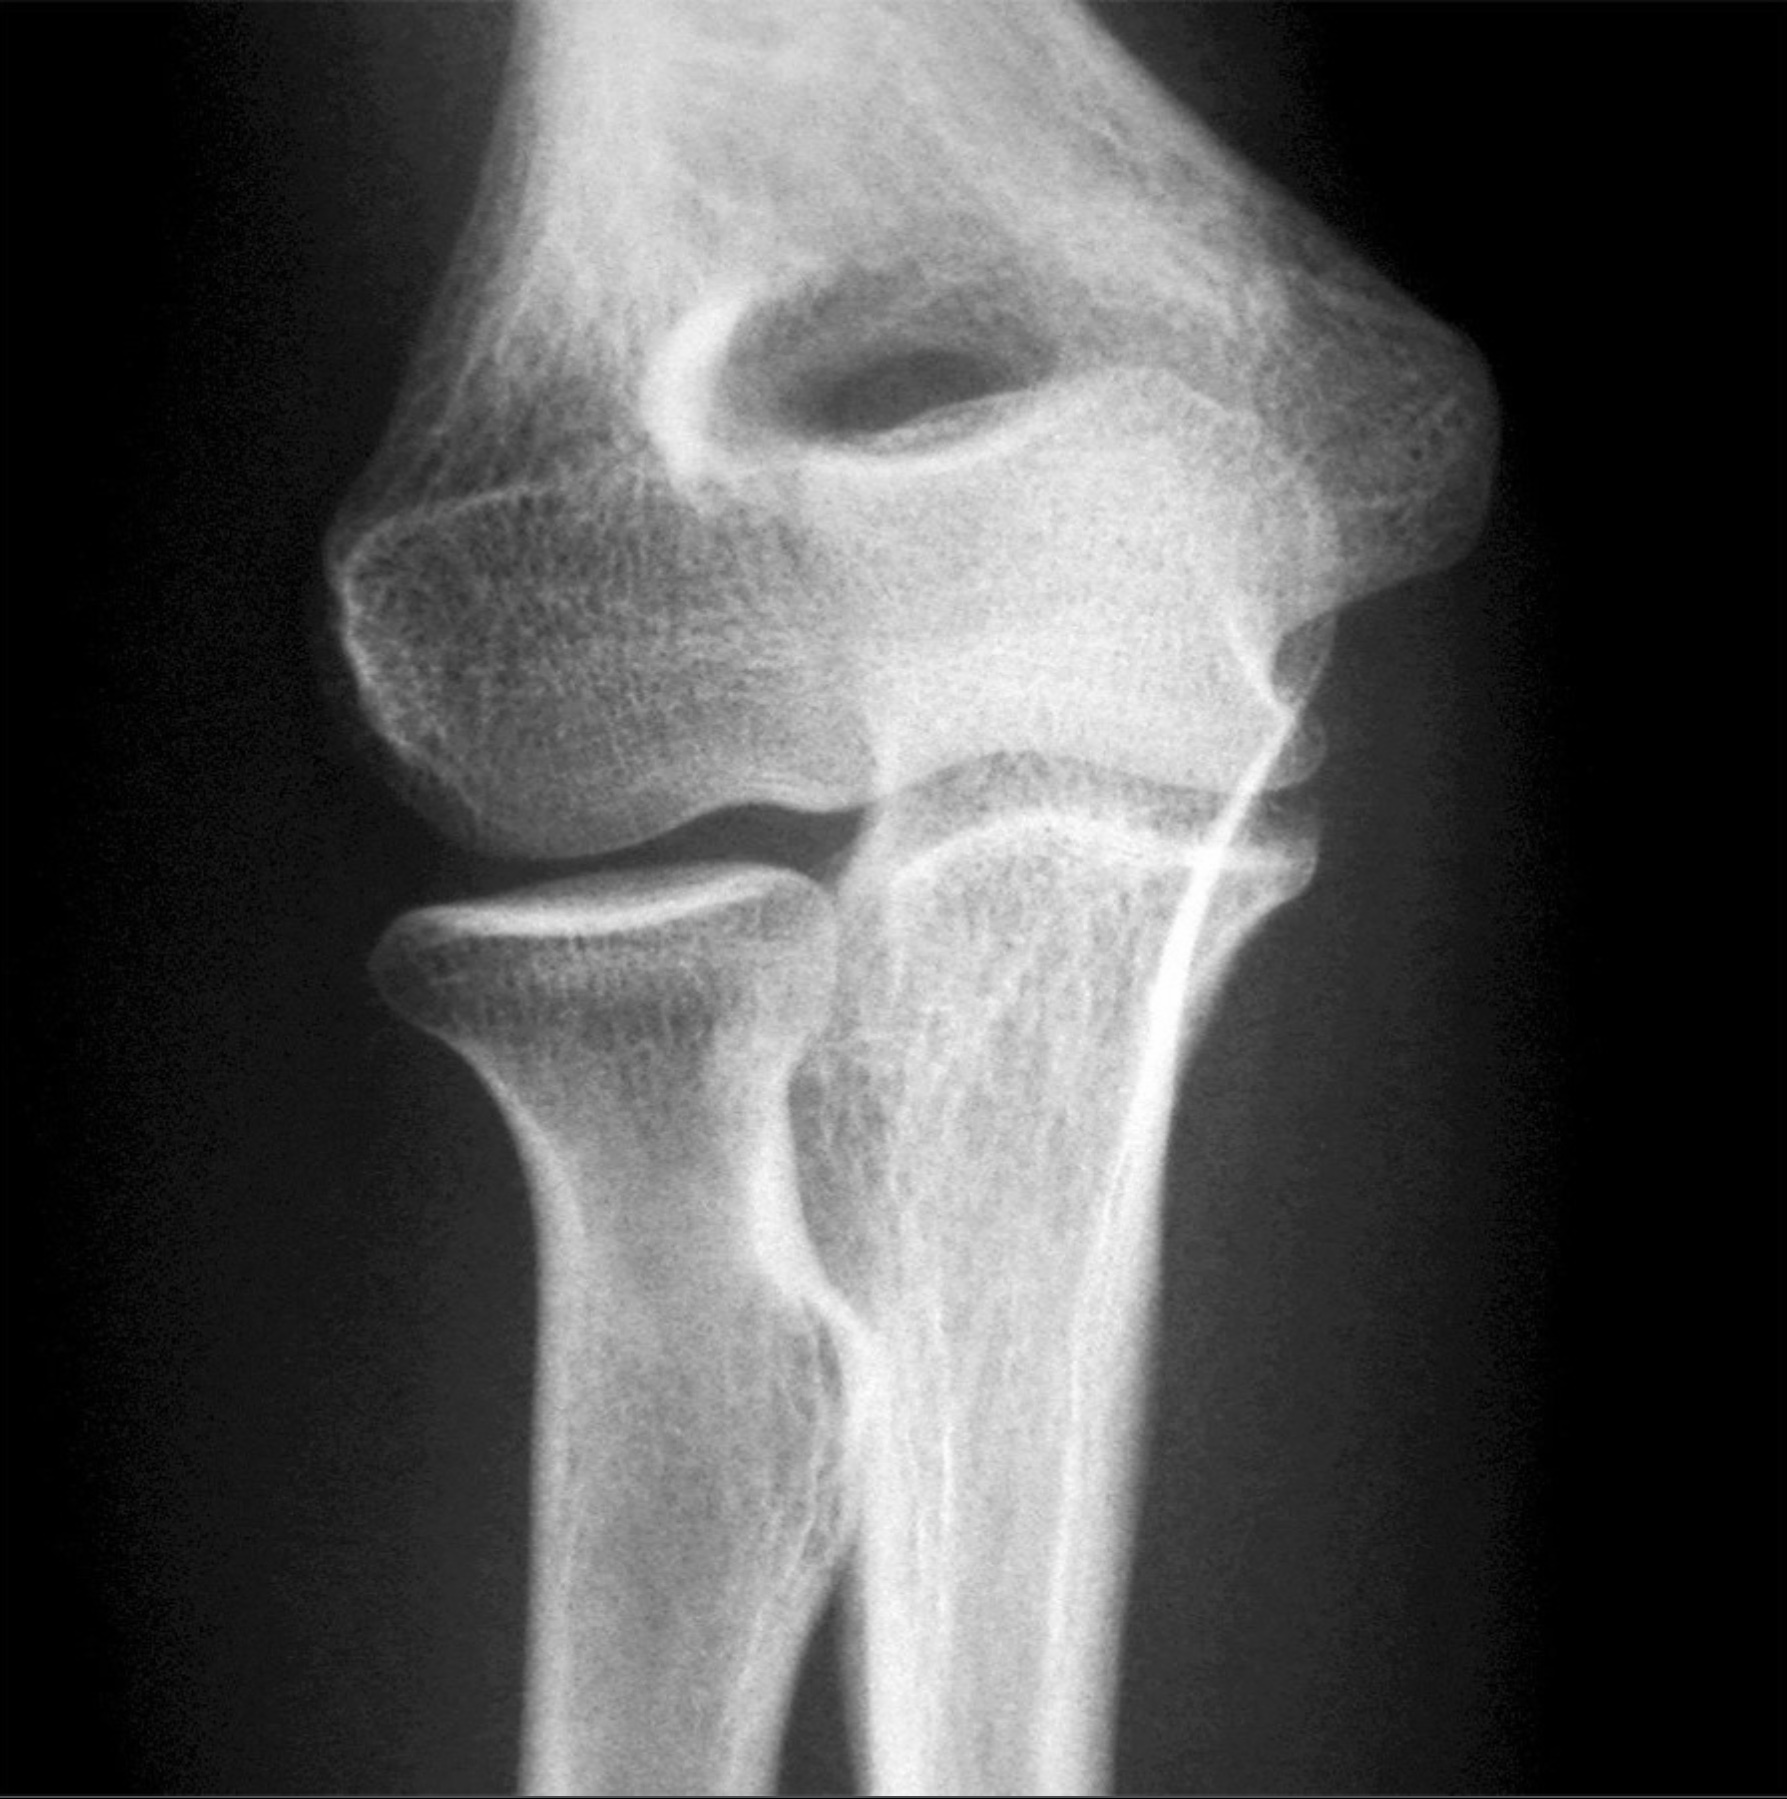

3. The elbow joint consists of three joints: the humeroradial, humeroulnar, and proximal radioulnar joints. Review the anatomy of the elbow joint. Include bones, articulations, ligaments, capsules, movements and limitations of movements. Relate the anatomy of the medial ulnar collateral ligament to Tommy John surgery.

11. On full flexion of the elbow, the coronoid process resides in the coronoid fossa and the radial head resides in the radial fossa. (True)

12. On full extension of the elbow, the olecranon process resides in the olecranon fossa. (True)

13. The lateral margins of the radial head articulates with the radial notch of the ulna. (True)

14. The head of the radius articulates with the capitulum of the humerus and the trochlear notch of the ulna articulates with the trochlea of the humerus. (True)

15. The medial collateral ligament of the elbow consists of anterior, posterior, and inferior bands (thickenings). (True)